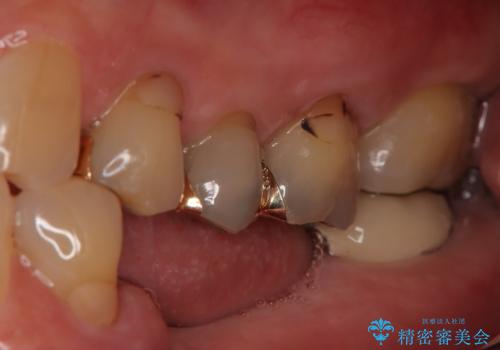

- 定期的に本院に通院されている患者様で、前歯の揺れがあると相談されました。下の奥歯が左右合わせて3本喪失されており、噛み合わせの負担が前歯にも集中していることを説明しました。右下6番の歯に関しては、事前の診査で十分な骨量がありましたのでインプラントを1本埋入しました。左下5番・6番にも本来はインプラントを埋入したかったのですが、骨量が十分でなく、骨を増やす処置をすると神経が近くリスクがあることから、審美性に配慮した金属のばねが見えないノンクラスプデンチャーを製作しました。また、このとき入れ歯を支える左下7番に根尖病変がありましたので、根管治療も行っております。(根管治療は当院院長で専門医を持つDr.林が担当しています。)治療終了後、約1年が経過しましたが、問題なく経過しており患者様も喜ばれていました。